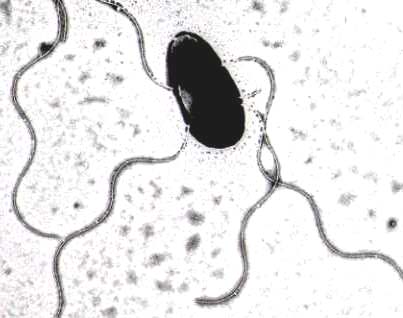

腸管出血性大腸菌の電子顕微鏡写真